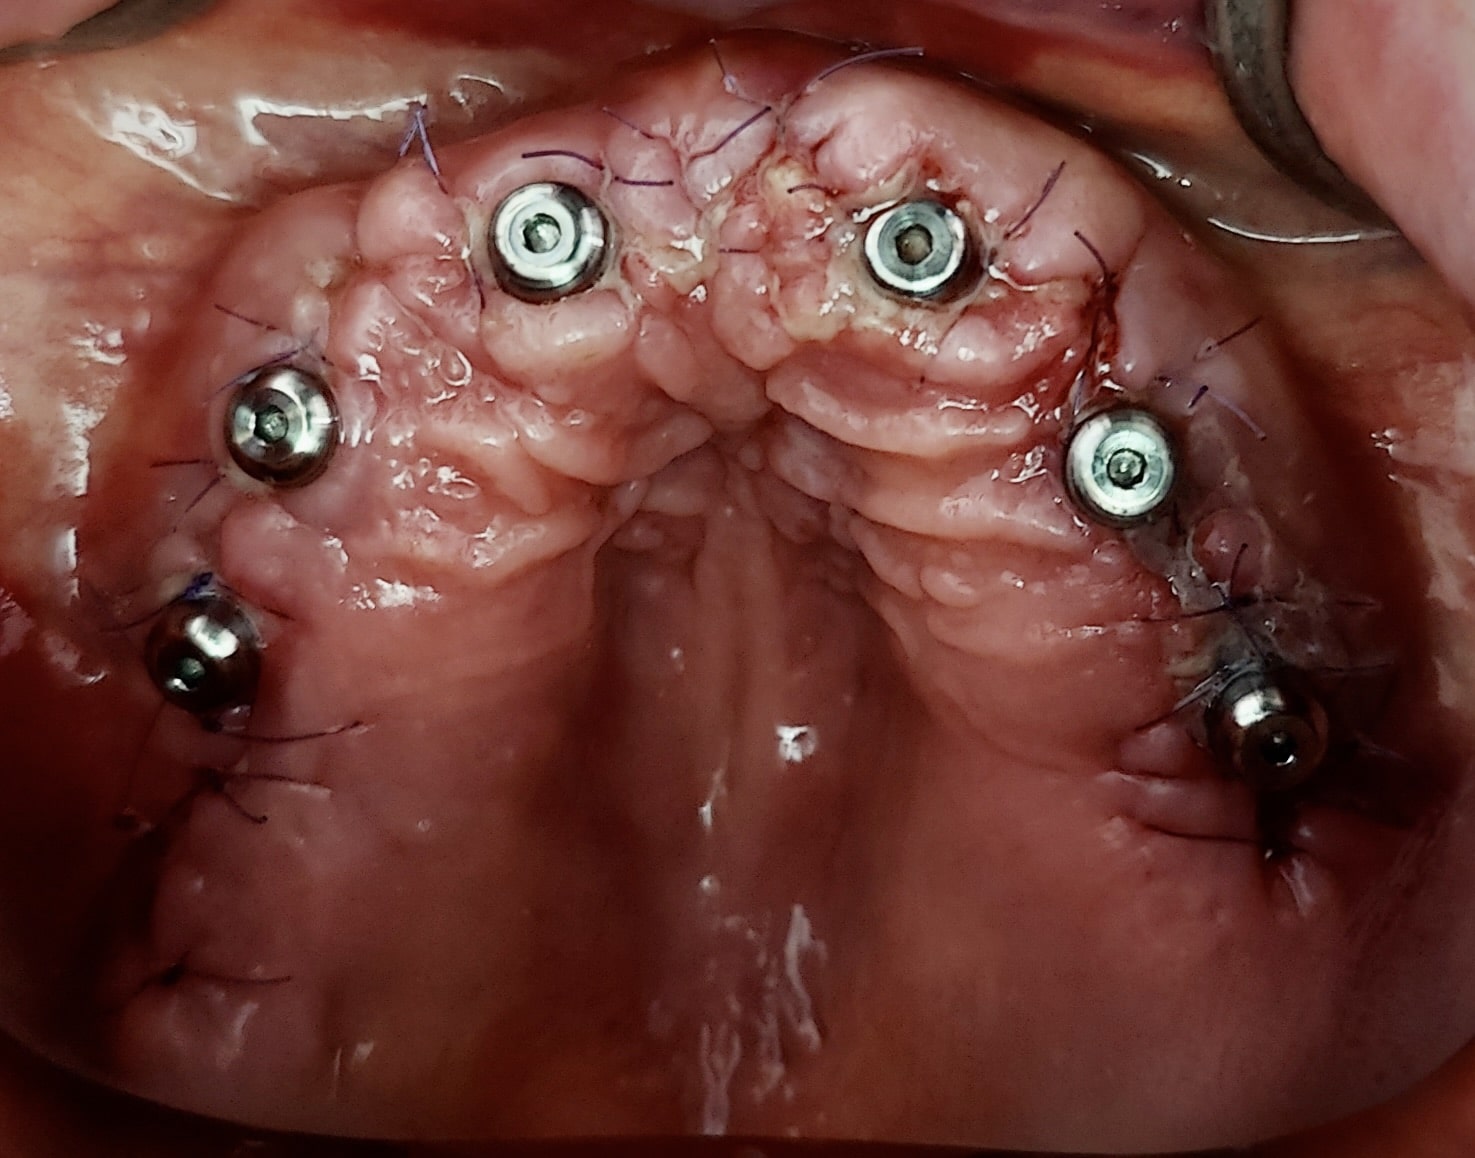

Le projet chirurgical permet d’envisager d’extraire l’ensemble des dents maxillaires et de placer six implants entre 15 et 25 pour la réalisation d’un bridge transvissé de 12 éléments :

La pose des implants devra (et pourra) être précédée d’une résection osseuse verticale suffisante après les extractions afin de remonter la ligne de transition implanto-prothétique à la limite du découvrement de la lèvre pour assurer un sourire plus esthétique. C’est ce dernier point qui décide la patiente à accepter ce plan de traitement de restauration globale.

Dans ce cas, la pose des implants a été réalisée sans guide chirurgical : ce sont les alvéoles déshabitées qui ont guidé les forages.

Radio de contrôle post-opératoire (les alvéoles ont été comblées par os autogène et BioOs) :

Notez que l’axe des implants distaux a permis d’éviter les sinus pour une simplification du protocole chirurgical